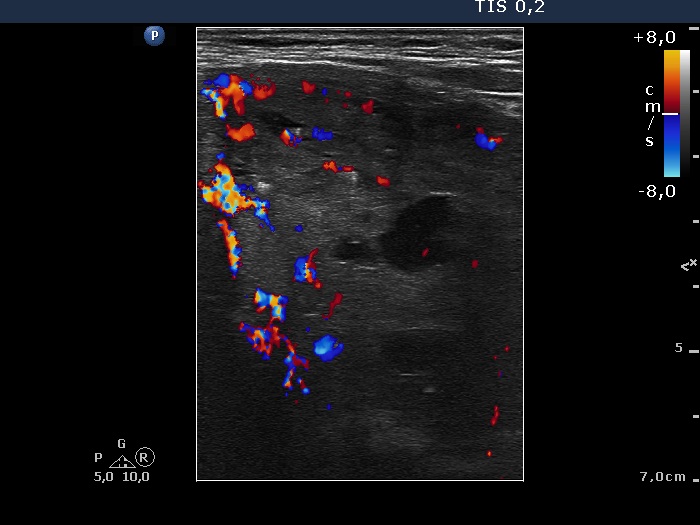

Ultrasonography. The right thyroid was composed of multiple discrete lesions with different echogenicities. The lobe was extremely enlarged with the dimension of 55x65 xminimum 120 mm (width, depth, and length, respectively) and spread retotracheal and substernal. The lower pole of the lobe could not be visualized while swallowing. The left thyroid was normal-sized and contained several hypoechogenic lesions. There was a moderately hypoechogenic nodule in the right lobe. The lesion presented neither halo nor perinodular blood flow.